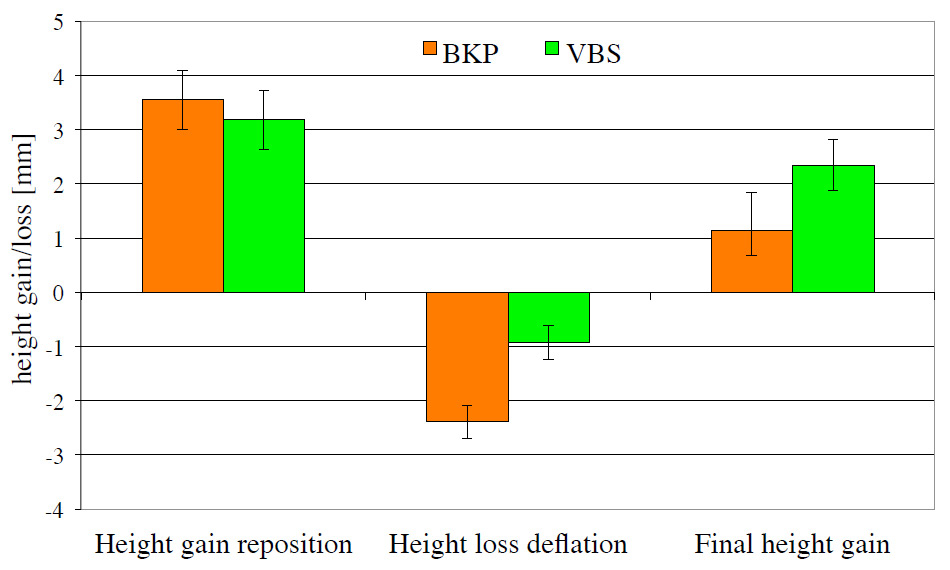

Normally VBCF are treated conservatively. However, in patients with severe pain stabilisation of the vertebral body with bone cementis now well accepted [4, 5]. The procedure consists in the injection of highly viscous cement directly into the fractured vertebral body (vertebroplasty) or by prior cavity creation with a balloon (kyphoplasty). These procedures do not allow real restoration of the compressed vertebral body, and further extension of the technique consists in vertebral body stenting, also called stentoplasty [6]. The principle resenbles that for vascular stents – a balloon mounted stent is expanded and in this way the vertebral body is lifted and, as a preliminary move, stabilised by the stent. For final stabilisation bone cement is injected. The stent can be expanded by some 400%, from 4.2 mm to 17 mm. (fig. 2). Based on in vitro experiments, greater height gain with the stent was demonstrated when compared to the balloon-only technique (fig. 3). For all patients with an osteoporotic fracture, assessment of bone metabolism and adequate medical treatment of osteoporosis are mandatory [7, 8].

Figure 3

The potential of height restoration and maintenance has been assessed in vitro on cadaver specimens. 24 vertebral bodies were fractured and kept under a preload of 110 N in order to maintain the “physiological” pressure. Then the height was restored using either ballon kyphoplasty (BKP) or vertebral body stenting (VBS). With the stent the relapse after deflation of the balloon is significantly lower which in turn leads to better height restoration in total.